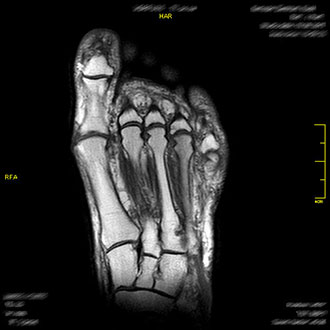

Die MRT des Fußes liefert hochpräzise Bilder von Knochen, Sehnen und Weichteilen.

Typische Befunde sind Hallux valgus, Hallux rigidus, Ermüdungsfrakturen (Marschfrakturen), Morton-Neuralgie, Plantarfasziitis oder Fersensporn.

Im Kernspin Zentrum Köln ist sie die Methode der Wahl zur Beurteilung schmerzhafter oder deformierter Fußgelenke – besonders für sportlich aktive Patienten.